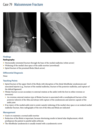

68yr old woman with diffuse bone pain

32